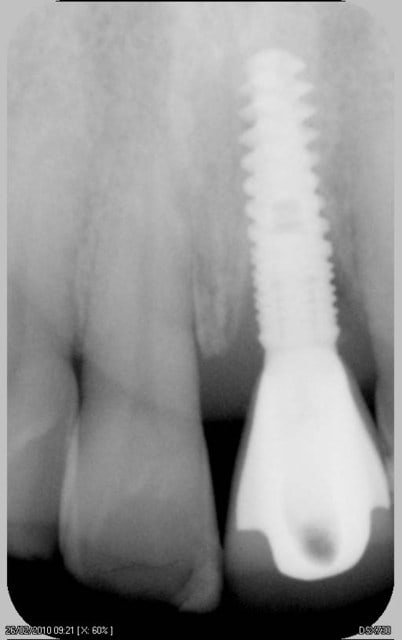

16/06/2010 à 16h05

comme promis

voici les cas vus ce mardi (il me manquait encore 10 patients: sur les 5 autres, tout est ok)

ps: la carie et le tartre sur la 7 ont été traités